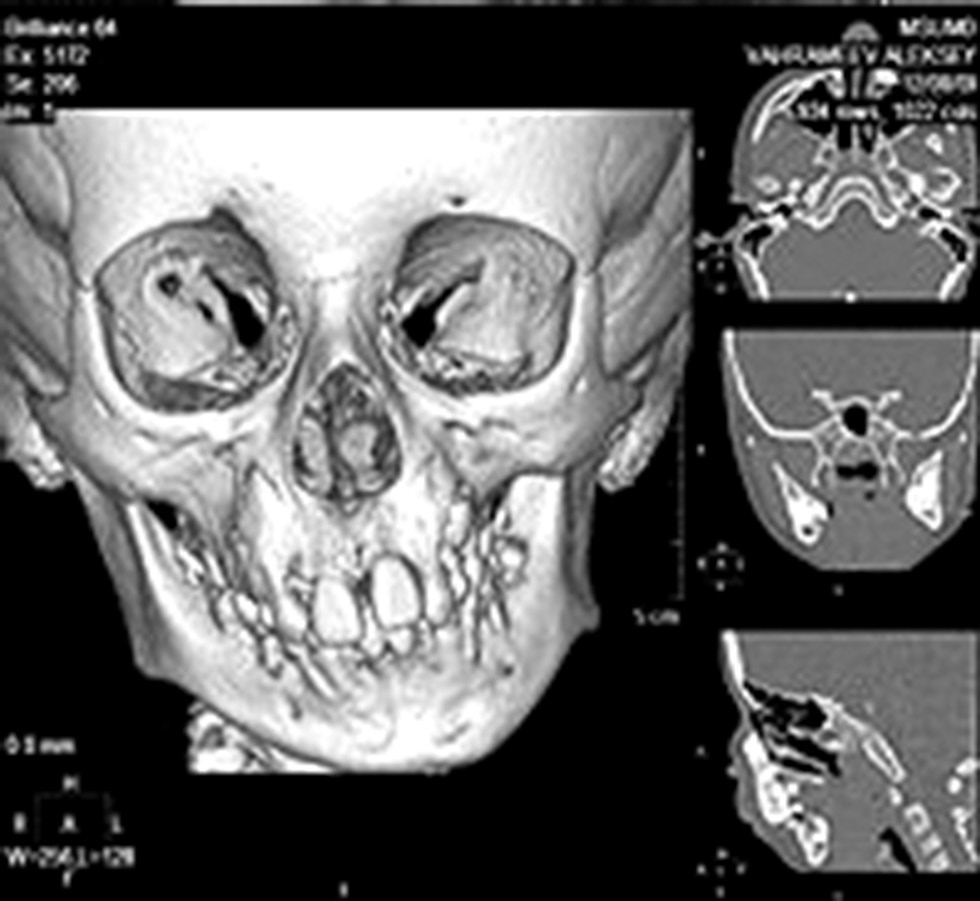

В качестве примера предоставим клинический случай применения классического механического КДА у пациента В., 7 лет, диагноз: «вторично-деформирующий остеоартроз левого височно-нижнечелюстного сустава. Недоразвитие тела, угла и ветви нижней челюсти слева, ограничение открывания рта до 1,5 см. Данное состояние возникло в результате родовой травмы, пациент наблюдался по месту жительства, деформация с возрастом усугублялась, ограничение открывания рта нарастало (рис. 3).

Рис. 3. МСКТ пациента В., 7 лет, до начала лечения.

Fig. 3. MSCT of the patient V., 7 years old, before the treatment.

Пациент поступил на лечение в клинику кафедры, где ему выполнили остеотомию ветви нижней челюсти слева с удалением патологических разрастаний; остеотомию в области угла и частично ветви нижней челюсти слева с одномоментным наложением однонаправленного механического КДА (рис. 4).

Рис. 4. Пациент В., 7 лет: a — удалённые во время операции патологические разрастания костной ткани; b — рентгенограмма с компрессионно-дистракционным устройством сразу после операции.

Fig. 4. Patient V., 7 years old: a — pathological bone tissue growths removed during the surgery; b — X-ray of the patient with compression-distraction device immediately after the surgery.